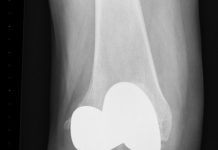

Risico op knieartrose al vroeg te bepalen

Al op betrekkelijk jonge leeftijd is te zien of iemand met knieklachten een verhoogde kans heeft om later knieartrose te ontwikkelen. Onder meer mensen...